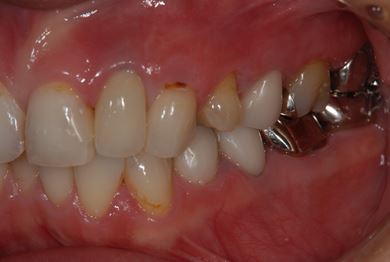

| 性別/年齢 | 女性 / 34歳 | ||||||||||||||||||||||||||||||||

| 主訴 | 現在痛みはなく、前歯の汚れを治したい。奥歯はブリッジを考えている。審美を考えているが、今治療をしたいというよりは、セラミックなど詳しいことがわからないので、計画や説明を伺いたい。 | ||||||||||||||||||||||||||||||||

| 治療方針 | 上前歯部分、セラミック治療にて審美的回復を行う。 | ||||||||||||||||||||||||||||||||

| 治療内容 | オールセラミッククラウン3本(オールセラミック用土台3本)、メタルボンドセラミッククラウン1本 | ||||||||||||||||||||||||||||||||

| 総治療費 | 562,800円 | ||||||||||||||||||||||||||||||||

| 治療期間 | 8ヶ月 |